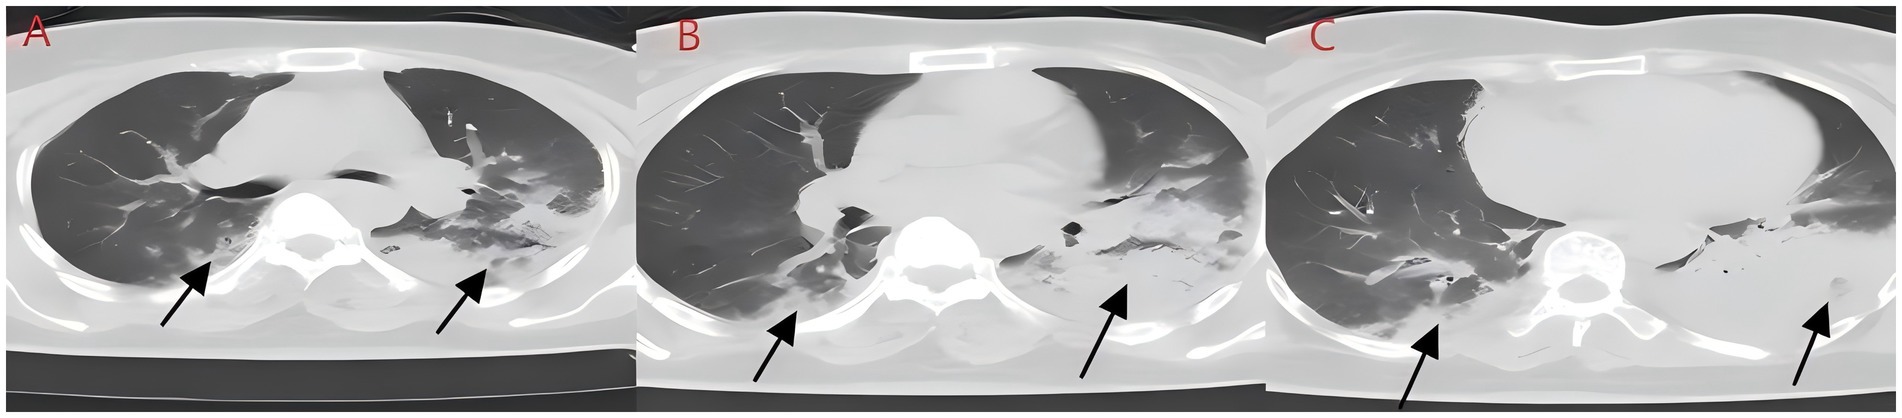

We present another case of a middle-aged Asian woman who was admitted to the hospital after drowning and inhaling a large amount of sewage. The patient inhaled stagnant wastewater from domestic sewage discharge. She showed noticeable chills and vomited a black, muddy substance while being transported. Upon admission, head, chest, and belly CT scans, along with related blood testing, were performed. Due to her critical condition, she was transferred to the ICU. Physical examination at admission revealed that her body temperature was 36.3 °C, pulse was 81 beats/min, respiration rate was 16 breaths/min, and blood pressure was 112/61 mmHg. The patient was conscious but had signs of fatigue and significant chills. Her scalp skin had a 3 × 1 cm tear. Her cardiac examination was normal; however, lung auscultation revealed bilateral wet rales, which were more pronounced in the left lung area. Furthermore, she had normal limb muscle strength and tone. There are no signs of meningeal irritation. The patient denied a history of underlying medical conditions or food or drug allergies. Emergency CT scan showed subarachnoid hemorrhage, and infectious lesions were observed in both lungs, with the left lung being primarily affected (Figure 2). The left lung also exhibits patchy, hyperdense shadows and a little pleural effusion. Moreover, her potassium levels were 2.96 mmol/L, and osmotic pressure was 288 mOsm/Kg. Similarly, the coagulation characteristics analysis revealed a D-dimer level of 3,990 μg/L. Arterial blood gas analysis showed her lactate level to be 2.50 mmol/L, pH (T) to be 7.37, pCO2 (T) to be 40.60 mmHg, and pO2 (T) to be 55.60 mmHg. Her complete blood count and C-reactive protein test results revealed that her white blood cell count was 19.77 × 109/L, whereas the C-reactive protein level was 0.51 mg/L. At admission, she was diagnosed with traumatic subarachnoid hematoma, aspiration pneumonia, type I respiratory failure, and drowning. After she was admitted to the ICU, she was given anti-infective drugs: cefoperazone–sulbactam (3.0 IV via VP every 8 h) combined with fluconazole (FLZ) injection [0.4 g via IV drip (IV gtt) once daily] to fight infection. After 2 days, the patient was re-examined due to stable vital signs, and chest CT revealed that lung infections had improved compared to the initial findings (Figure 3). After consultation with a clinical pharmacist, cefoperazone–sulbactam was changed to biapenem (0.3 g IV gtt qd every 8 h) combined with FLZ (0.4 g IV gtt qd) to remove the microorganisms. After 5 days, due to recurrent fever, she was transferred to the respiratory department and her anti-infection regimen was adjusted to oral therapy: meropenem (Mpm; 1 g IV every 8 h) combined with voriconazole tablets (400 mg every 12 h). After ruling out contraindications, tracheoscopy was performed on LB2 and LB3, with brushing and BAL of the left upper lobe. Furthermore, cytology, acid-fast stain, cell differential count, culture, and mNGS analysis of the lavage fluid were performed. Both lungs indicated improved infection lesions in the chest re-examination (Figure 4). The patient was discharged after 12 days of admission due to her inability to pay hospitalization expenses. The lavage fluid mNGS revealed the presence of T. whipplei (sequence number: 4683) and Aspergillus flavus (sequence number 9). During hospitalization, the primary medication was a dimorphic dose, but only the last dose was consistent with the mNGS report (Figure 5).

Figure 2. (A–C) Chest CT after aspiration of sewage (case 2). Diffuse infection can be seen in both lungs, mainly in the lower lobe of the left lung, with obvious bronchial inflation signs.